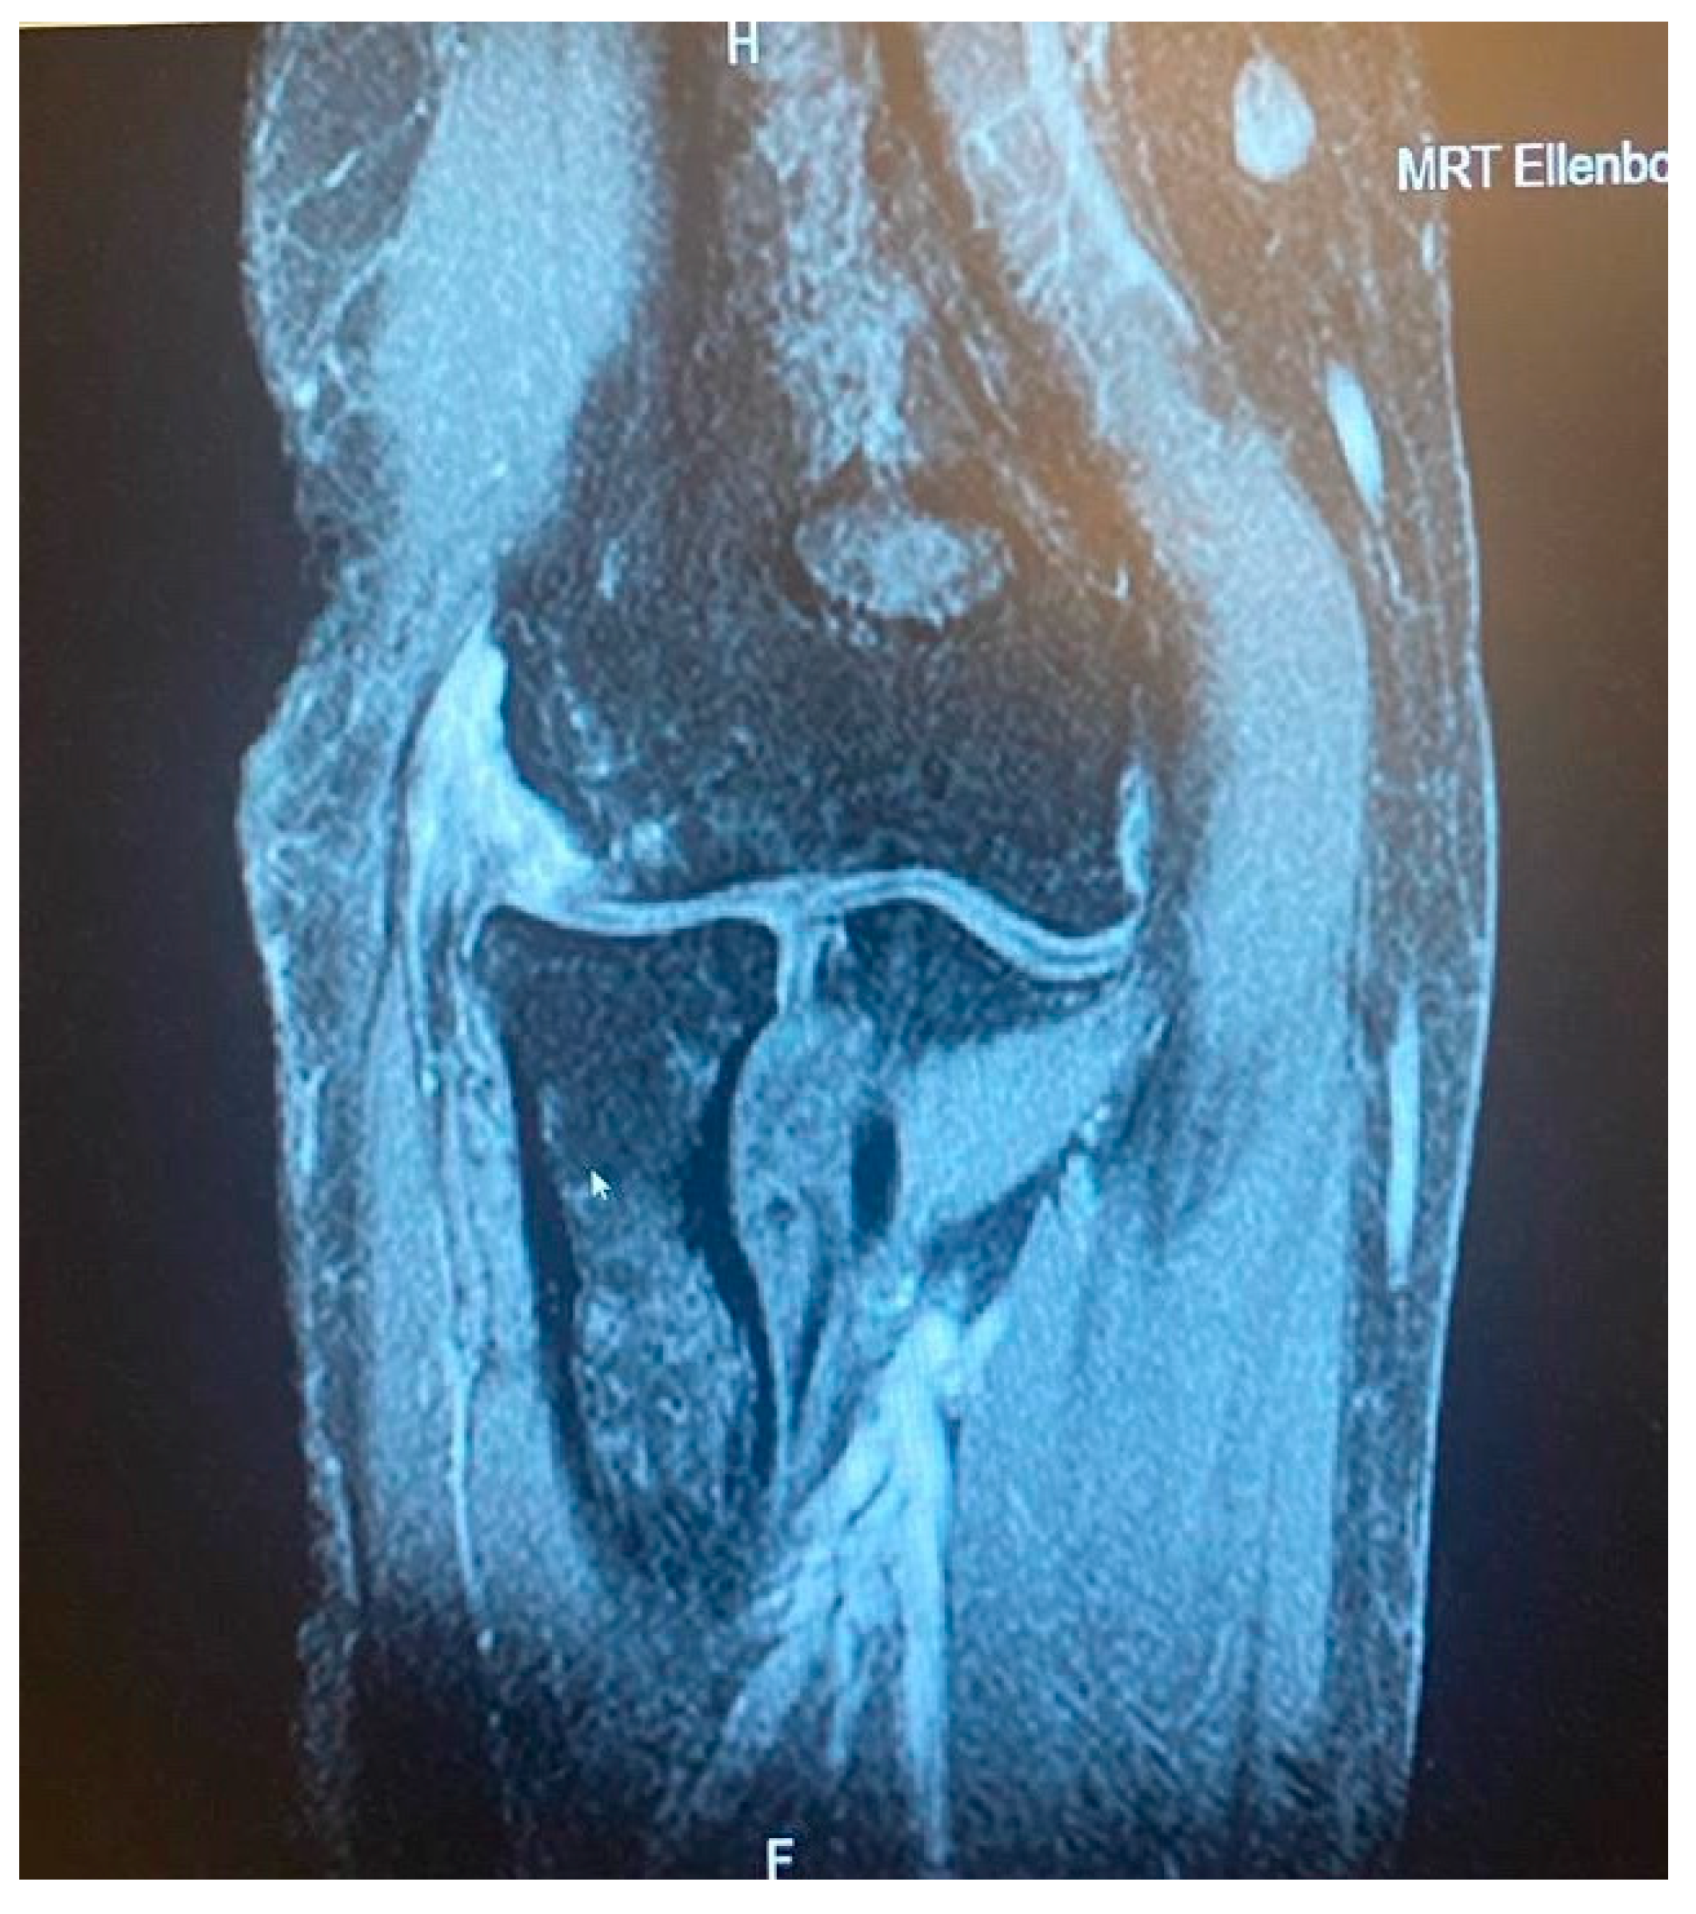

Figure 6.

Complete CEO rupture with retraction and poor tendon quality [courtesy of C.K.].